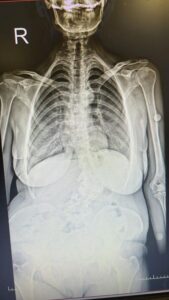

Omurganın sağa veya sola eğrilmesi sonucu ortaya çıkan skolyoz hastalığı, çocukluk ve ergenlik dönemlerinde sıkça görülürken, yetişkinlerde de ortaya çıkabiliyor. Bu rahatsızlıkla mücadele eden Türkiye’nin dört bir yanındaki vatandaşların Bolu Abant İzzet Baysal Üniversitesi Eğitim ve Araştırma Hastanesi’ne tedavi olmak için geldiğini belirten Ortopedi Klinik Sorumlusu Prof. Dr. Cengiz Işık, tedavi olanların tavsiyesi üzerine 81 ilden hasta geldiğini ifade etti. Tedavi esnasında öncelikli gayelerinin hastalığın ilerlemesini önlemek olduğunu belirten Işık, “Tedavi yöntemlerinin en büyüğü, en önemlisi ve en çok yapılanı da mümkün oldukça hastaya koruyucu hekimlik yapmak. Cerrahi müdahaleden önce hastalığın önlenmesini sağlamak” dedi.

Tavsiye üzerine Türkiye’nin 81 ilinden hasta geldiğini ifade eden Işık, “Omurgada oluşan skolyozun tedavisinde birçok tedavi yöntemi var. Tedavi yöntemlerinin en büyüğü, en önemlisi ve en çok yapılanı da mümkün oldukça hastaya koruyucu hekimlik yapmak. Cerrahi müdahaleden önce hastalığın önlenmesini sağlamak. Biz daha çok mümkün oldukça nasıl ilerlemesini durdurabileceğimiz, nasıl yavaşlatabileceğimizle uğraşıyoruz. Yılda ortalama 150-200 civarında omurga cerrahisi yapıyoruz. En çok gelen kısım Batı Karadeniz bölgesi; Bartın, Zonguldak, Karabük, Düzce, Bilecik gibi iller. Batı Karadeniz’de tekiz. Sadece Batı Karadeniz değil, Antalya’dan, Manisa’dan, Van’dan gelen de var. Bugün gelen hastalardan bir tanesi mesela Adana’dan gelmiş. Birkaç ay önce ameliyat ettiğimiz hasta da var. Bursa, İstanbul, Ankara’dan gelen de oluyor, tabii her yerden hasta geliyor. En çok yoğunluk olarak söylediğimiz tabii ki Batı Karadeniz. Herhalde ikinci sırada da İstanbul olur. Çünkü İstanbul’da tedaviye ulaşmak biraz daha zor olduğu için tedavi edilenlerin yakınları tarafından yönlendirilen kişiler oluyor bize” dedi.